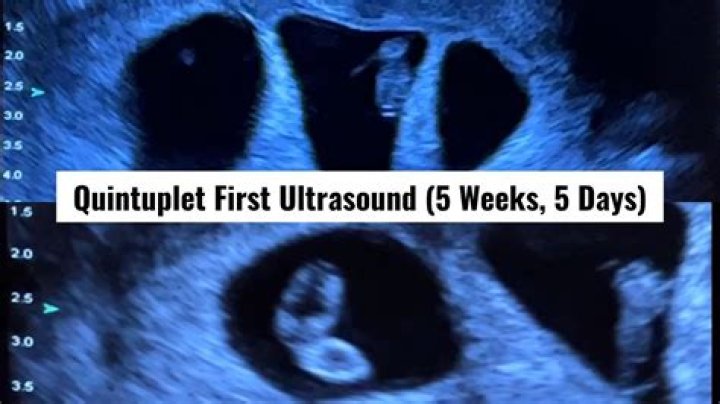

At this stage, the only things you'll likely see are the yolk sac and the gestational sac. It's possible that the sonographer might be able to point out the embryo, which at this stage is likely a tiny white curled object. Surrounding the embryo is the yolk sac, which will look like a small white circle.

Can 5 weeks pregnant scan?

In week 5 of your pregnancy the embryo is approximately 1.3mm from the crown of the head to the rump but is very difficult to see and measure at this stage using ultrasound. You'll find that the ultrasound is the best way to measure and monitor a baby during your pregnancy.

At 5 weeks into pregnancy things are so small there is very little to see on ultrasound. Even at 6 weeks it can be difficult to see an embryo with some people.

Can you see heartbeat at 5 weeks 5 days?

A fetal heartbeat may first be detected by a vaginal ultrasound as early as 5 1/2 to 6 weeks after gestation. That's when a fetal pole, the first visible sign of a developing embryo, can sometimes be seen. But between 6 1/2 to 7 weeks after gestation, a heartbeat can be better assessed.